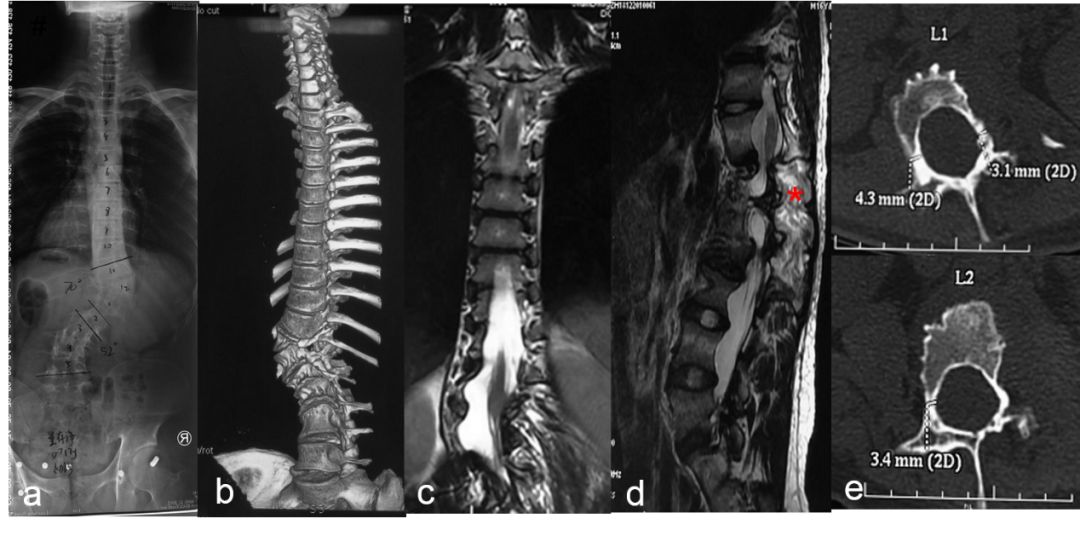

NF1患者脊柱在形态学上的异常主要包括椎体楔形变、椎体扇贝样改变(图6)、椎弓根狭窄(图7)、椎弓根间距增宽、横突纺锤形改变以及椎管扩大等。以上征象很少单独出现,往往合并存在。

图. 男性,7岁,NF1伴脊柱侧凸;X线示腰椎侧凸畸形(a), CT示椎体及椎板椎弓根破坏,椎管扩大(b、c);MRI示椎管扩张,椎旁肿瘤(c、d);CT横断面示椎弓根发育不良,椎体边缘破坏(e)